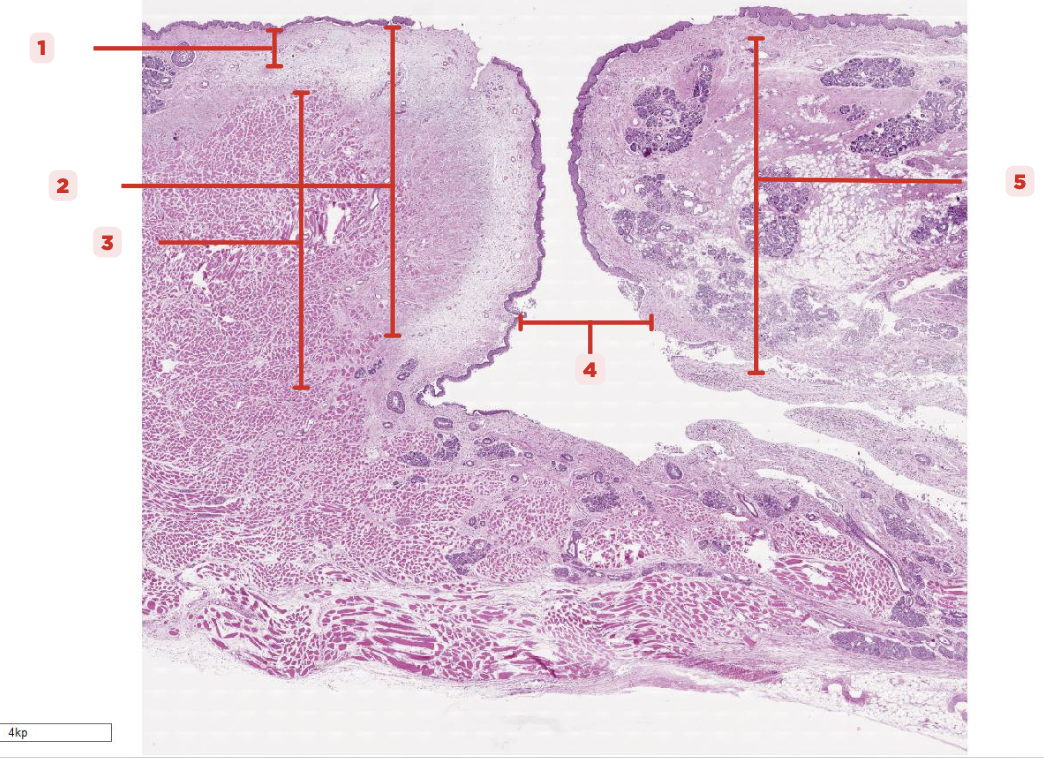

Identify the structure labeled as 1.

Laryngeal Ventricle

Space that separates the true and false vocal cords (#4)

True Vocal Cord

The #2 consists of a lamina propria that includes the vocalis ligament and a group of skeletal muscles known as the vocalis muscle.

Vocalis Ligament

Identify the structure labeled as 1.

True Vocal Cord

Identify the structure labeled as 2.

Vocalis Muscle

Identify the structure labeled as 3.

Laryngeal Ventricle

Identify the structure labeled as 4.

False Vocal Cord

Identify the structure labeled as 5.